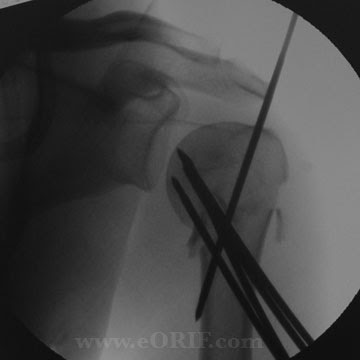

Proximal Humerus Fracture Crpp 23615 Eorif